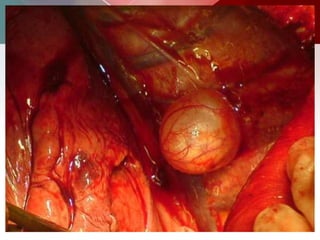

b) Hydatid cysts:

 Hydatid cysts may be solitary or multiple, the number

depending mainly on the amount of ova ingested and

the number of embryos filtered through the liver and

lungs.

 A centrally located cyst is said to be usually round,

but may become oval or polycyclic. Inferior lobes most

commonly affected

 Intact: ruptured= 3:1

Outer acellular laminated membrane, Germinal membrane& Protoscolices, attached and

budding from the membrane